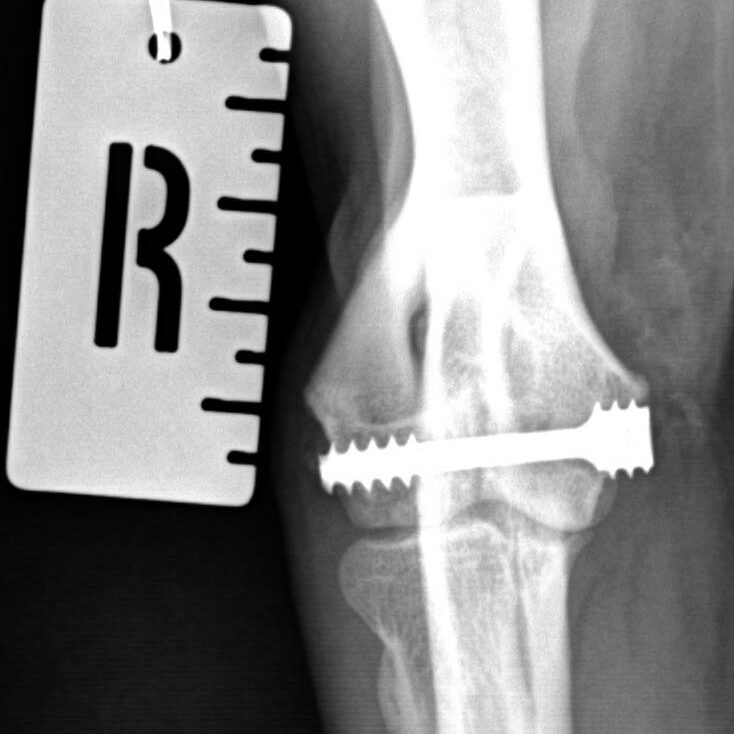

CT is the most common means of diagnosing HIF. Radiography (X-rays) will miss some of them, but if you can see one on a radiograph then further tests might not be required. Other possible causes of lameness, eg elbow dysplasia, might also need to be considered.

Most Specialists are likely to advise placing a screw across the humeral condyle, especially if your dog is limping and/ or there is elbow pain. The purposes of the screw are to prevent movement and instability and therefore improve the lameness, and to reduce the risk of the bone breaking completely.

Two of Movement’s Specialists, Ben Walton and John Innes, designed and clinically tested the humeral intracondylar repair system (HIRS) for the treatment of HIF in Spaniels and, the clinical results were published in 2020.

Placing the screw accurately is very important to avoid damaging the joint. We will often use custom, patient-specific, 3D-printed surgical guides like THESE, or a careful planning method like THIS.